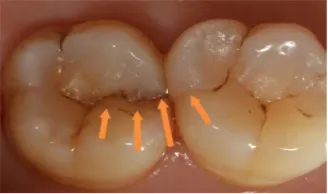

牙隐裂( Cracked tooth)(如图1、图2所示) 指牙冠表面出现的不易察觉的非生理性微小裂纹,是从牙冠开始并延伸到龈下的不完全折裂,通常为近远中方向,裂纹可以延伸至一个或两个边缘嵴并穿过近端表面,有可能累及牙髓或牙根,导致牙髓和根尖周病变。

图1图2:隐裂牙及裂纹